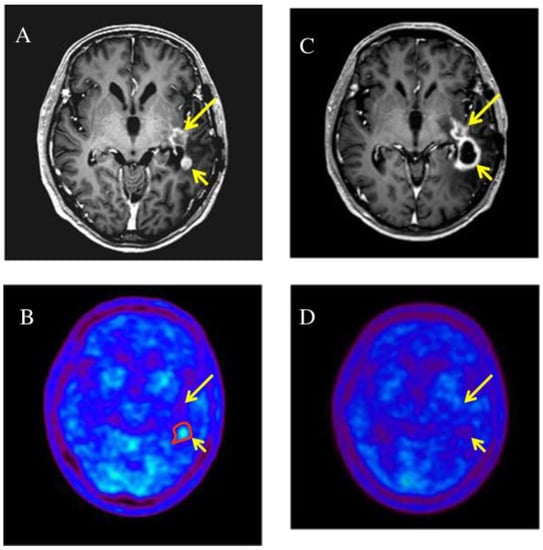

- Grosu, A.L.; Weber, W.A.; Franz, M.; Stärk, S.; Piert, M.; Thamm, R.; Gumprecht, H.; Schwaiger, M.; Molls, M.; Nieder, C. Reirradiation of recurrent high-grade gliomas using amino acid PET (SPECT)/CT/MRI image fusion to determine gross tumor volume for stereotactic fractionated radiotherapy. Int. J. Radiat. Oncol. Biol. Phys. 2005, 63, 511–519. [Google Scholar] [CrossRef] [PubMed]

- Miwa, K.; Matsuo, M.; Ogawa, S.; Shinoda, J.; Yokoyama, K.; Yamada, J.; Yano, H.; Iwama, T. Re-irradiation of recurrent glioblastoma multiforme using 11C-methionine PET/CT/MRI image fusion for hypofractionated stereotactic radiotherapy by intensity modulated radiation therapy. Radiat. Oncol. 2014, 9, 181. [Google Scholar] [CrossRef] [Green Version]